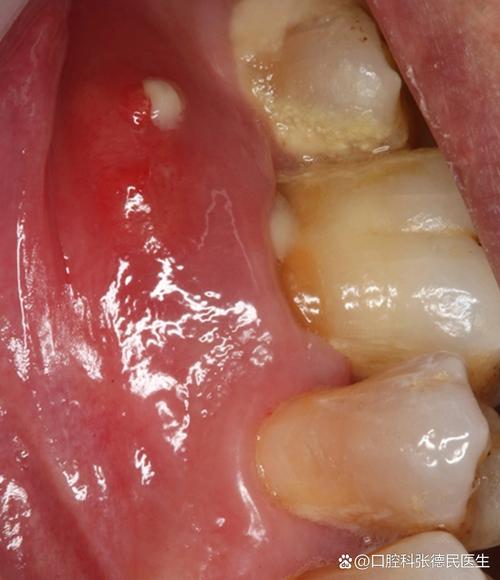

口腔牙床上长了一个包

牙床上的“包”在医学上通常被称为“脓肿”或“瘘管”,是身体对感染的一种反应,最常见的原因是:

牙根尖周脓肿

这是最常见的原因,通常由严重的蛀牙(龋齿)发展而来。

- 病因:蛀牙深入牙髓(牙神经),导致牙髓感染坏死,感染物质通过牙根尖孔扩散到牙根周围的组织,引发炎症和脓液积聚,形成脓肿。

- 特点:

- 包块通常位于牙齿的牙龈根尖区域(即牙齿在牙龈线下方的投影处)。

- 牙齿会有明显的浮起感,咬合时疼痛。

- 牙齿可能变色或有深大的蛀洞。

- 可能伴有自发性的、跳痛的疼痛。

- 严重时可能伴有发烧、面部肿胀。